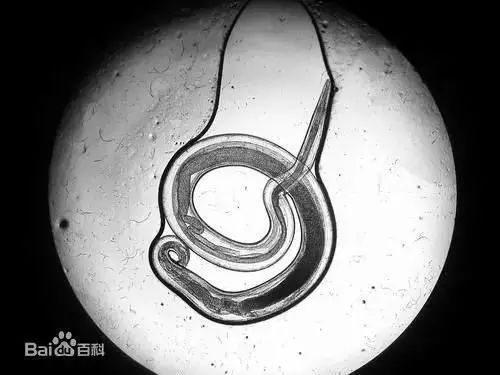

▲结膜吸吮线虫(资料图)

医生介绍,冈田绕眼果蝇是我国结膜吸吮线虫的中间宿主,也是本病的传播媒介。通常是狗或猫等睡觉时被果蝇接触眼部取食而感染。寄生于人眼,可引起结膜吸吮线虫病,这种病例多为散发,并不常见。

成虫寄生于人眼结膜囊内

▲结膜吸吮线虫(来源百度百科)